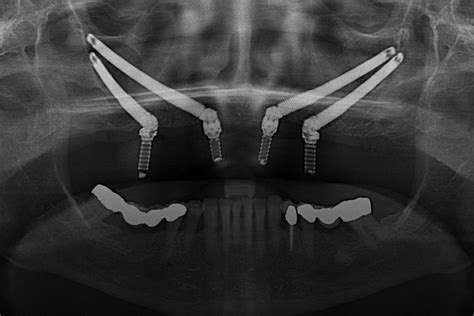

En los últimos años, la Implantología se ha convertido en una alternativa terapéutica imprescindible en la Odontología moderna. Los avances más destacados son en el diagnóstico y planificación de los casos, la mejora de la técnica quirúrgica y el control de la periimplantitis; todo ello de la mano de las nuevas tecnologías CAD/CAM.

La Implantología se encuentra en un momento magnífico, siendo una de las disciplinas de la Odontología que más ha progresado en los últimos años. La industria y los profesionales se han volcado en el avance de la misma de manera continuada.